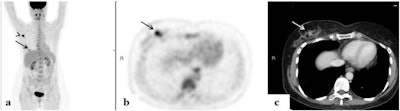

FDG-avid multifocal breast lesions. An 84-year-old woman with a multifocal cancer in the left breast and multiple bone FDG-avid metastatic lesions. FDG-PET/CT: maximum intensity projection (MIP) (a), a representative PET (b), and CT axial slices (c). Images courtesy of Surgical Oncology.

FDG-avid multifocal breast lesions. An 84-year-old woman with a multifocal cancer in the left breast and multiple bone FDG-avid metastatic lesions. FDG-PET/CT: maximum intensity projection (MIP) (a), a representative PET (b), and CT axial slices (c). Images courtesy of Surgical Oncology.In addition, distant FDG-avid lesions were detected in 33 patients (10.2%). Seven patients without distant metastases had FDG-avid supraclavicular lymph node involvement and four had FDG-avid internal mammary lymph nodes.